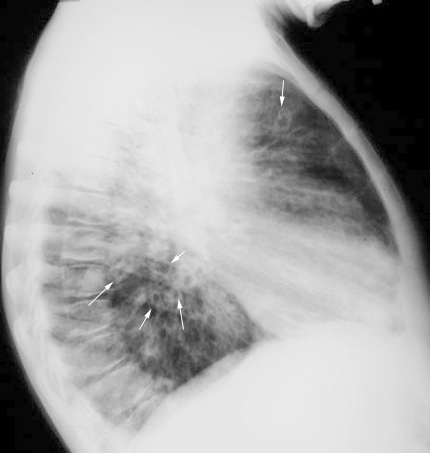

Case 4

Lateral

Labeled Image

What are the contents of a cavity?